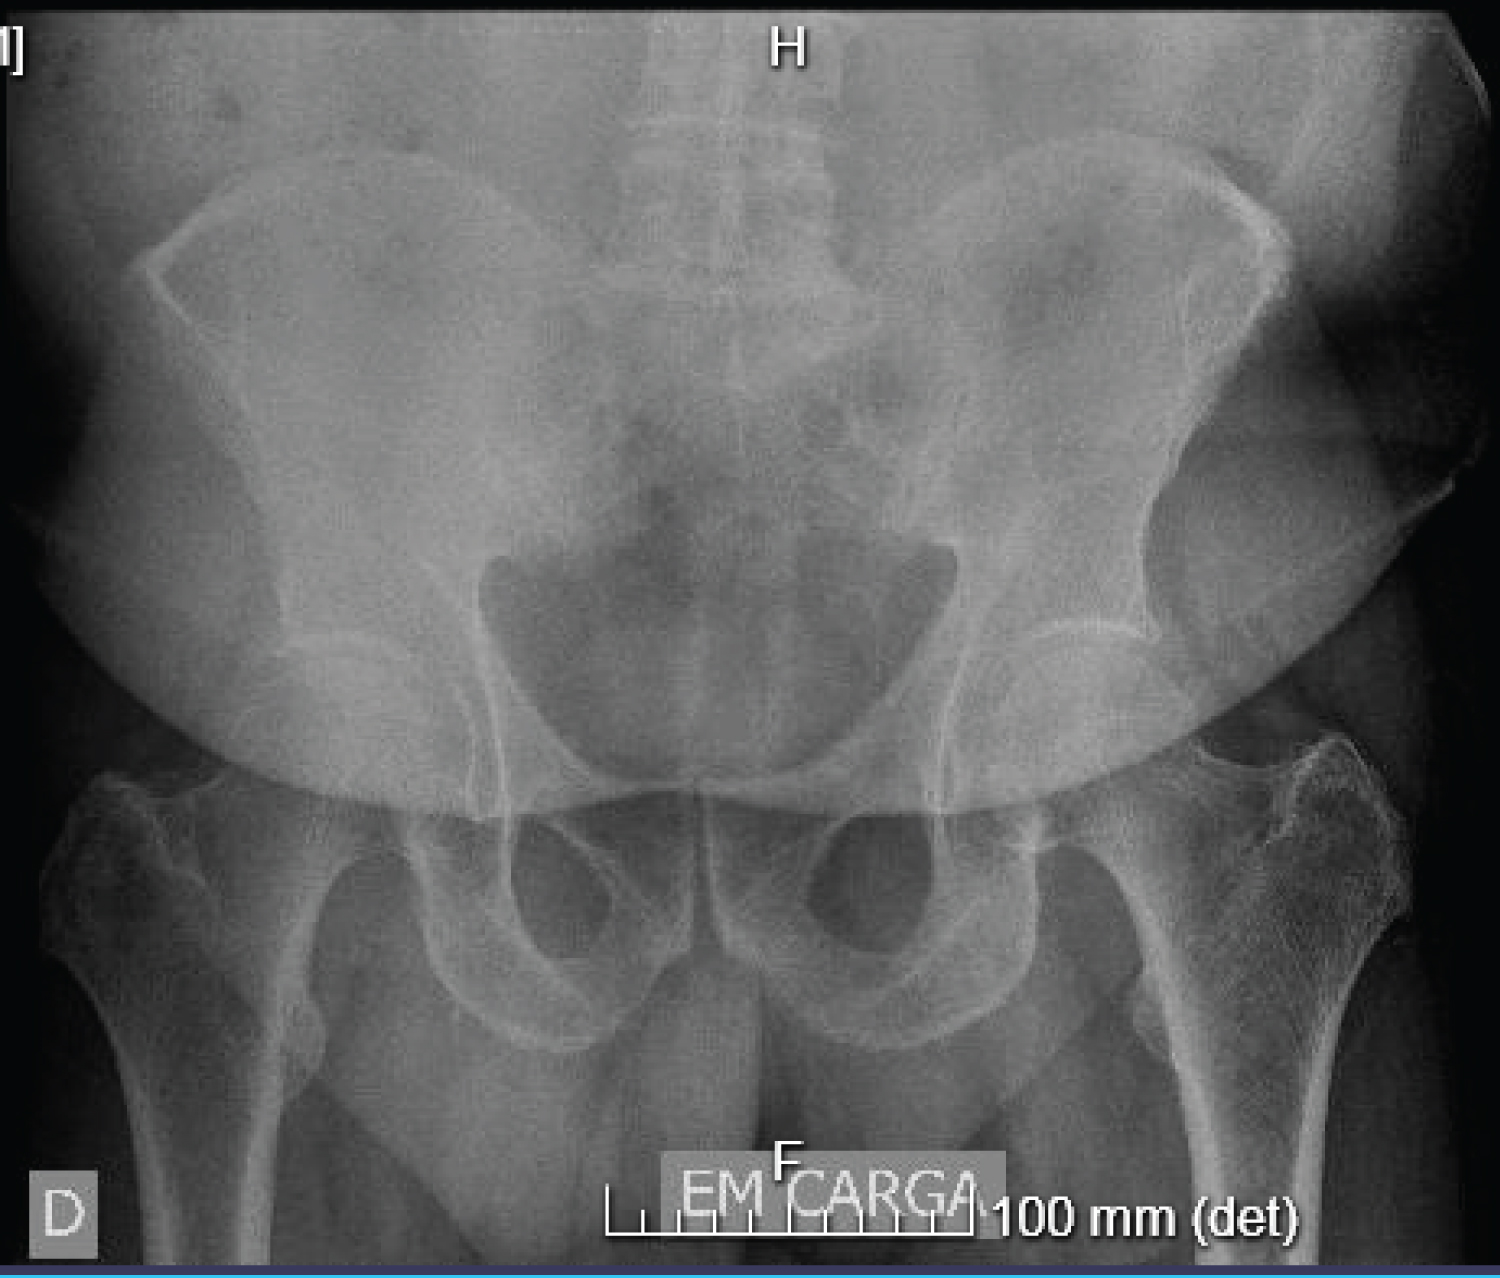

The X-ray (Figure 1) shows degenerative changes in both hips and SIJ (with some periarticular sclerosis and blurring of the SIJ margins).

Figure 1: Lumbar and Hip Radiography, from September 2019. View Figure 1

Imaging studies are of limited diagnostic value in SIJ pain, but they should be considered in the setting of "red flags" (fracture, infection, malignant or rheumatologic causes). The initial imaging modality for the diagnostic remains the conventional radiography. A CT scan can be useful for bone-related changes, whereas MRI is the gold standard when considering an inflammatory disorder. Also, some studies suggest that most of those who met the strict diagnostic criteria for SIJ pain had at least one abnormality on their hip radiography [1]. This suggests that clinicians should consider hip pathology in the differential diagnosis.

Our patient had confounding factors for the diagnosis, like the hip flexion and rotation limitation and the inguinal irradiation of pain, that might indicate hip osteoarthritis. However, considering all the findings and IASP criteria, there was a high suspicion of a mainly SIJ source for the complaints, so it was our first goal to prove it by performing a diagnostic test with an ultrasound-guided infiltration.